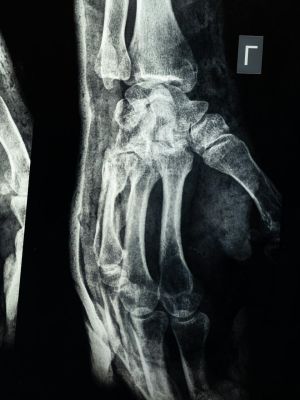

Multislajsni CT skener zglobova omogućava detaljan prikaz kostiju i mekih struktura koje učestvuju u pokretu. Na snimcima se jasno sagledavaju površine zgloba, okolni ligamenti i prostori između kostiju, pa se lekarima pruža pouzdan uvid u promene koje ne mogu da se uoče običnim rendgenskim snimkom.

Koje promene se mogu uočiti na snimcima

Pregledom se mogu otkriti oštećenja kostiju, promene u zglobnim površinama, nakupljanje tečnosti i prisustvo izraslina.

• Prelomi i nepravilnosti u položaju kostiju zgloba

• Degenerativne promene u zglobnim površinama

• Znaci zapaljenja i prisustvo tečnosti u zglobu

• Izrasline i nepravilnosti u strukturi tkiva

• Promene na okolnim mekim tkivima